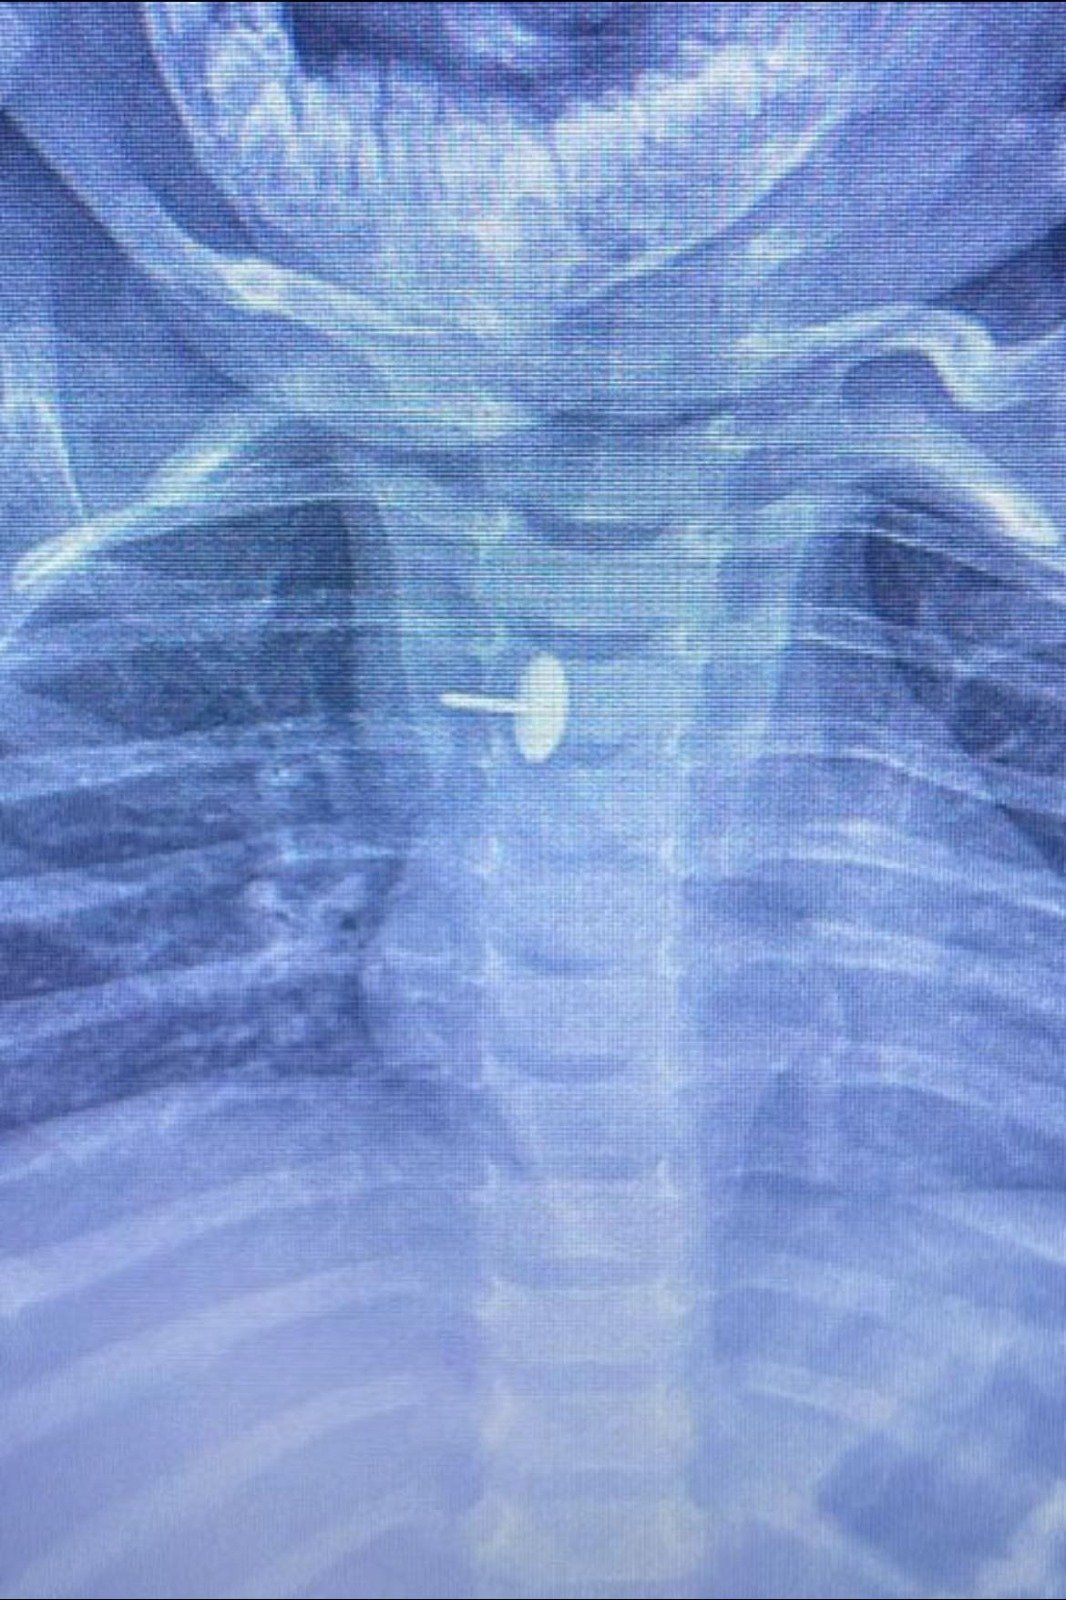

نجح فريق قسم جراحة الأطفال، بمستشفى الأطفال التخصصي ببنها، بمحافظة القليوبية، بقيادة الدكتور محمد متولي رئيس قسم جراحة الأطفال، في إجراء عملية دقيقة لاستخراج دبوس ضغط من مريء طفلة عمرها سنة و7 أشهر، كانت قد ابتلعته منذ 6 أشهر.

الجسم الغريب استقر داخل جدار المرئ

كشفت مستشفى الأطفال التخصصي ببنها، في بيان لها، أن الجسم الغريب استقر داخل جدار المريء، مما تسبب في عدم قدرة الطفلة على البلع طوال هذه الفترة، وجعل حياتها في خطر دائم. استخدام أحدث الأجهزة في الجراحة

دبوس ضغط فى مرئ طفلة